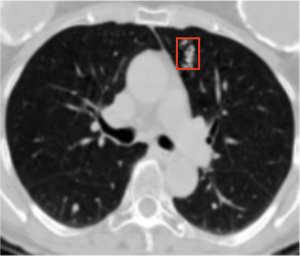

Before we dive deeper into enforcing causal alignment, we have to get to know the data we're working with. Our images are slices of lung CT scans which might or might not contain malignant lung nodules.

- x: The image

- y: The image's label. y=1 means there is a malignant nodule, y=0 means there is no malignant nodule.

- m: The doctor-annotated area where the nodule is. Annotated as a red box in the image.

We are trying to construct a function f which looks at our image x and determines the correct label y. To ensure causal alignment, we also want to make sure that f is "paying attention" to the abnormal area m, and not some other part of the image.